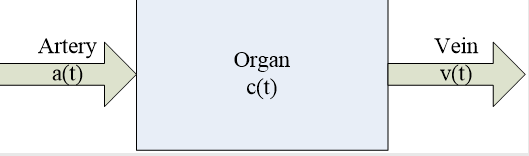

a、脑部灌注增强造影

脑部的生理性功能活动以及病理活动与组织血流微循环状态密切相关。

脑部灌注增强造影对脑部组织生理、病理变化非常敏感。

可了解血液动力学及功能上的变化。

可比CT平扫等常规影像技术更早更准确地诊断脑组织缺血等疾病。

灌注成像的理论基础

核医学放射性示踪剂稀释理论以及中心容积定律:

血容量=血流量×平均通过时间

通过直接测量CT值随时间的变化曲线获得组织内碘对比剂浓度随时间变化的曲线(Time-Density Curve, TDC),从而获得:

脑血流量(Cerebral Blood Flow, CBF)

脑血容量(Cerebral Blood Volume, CBV)

平均通过时间(Mean Transit Time, MTT)

达峰时间(Time TO Peak, TTP)

灌注图像后处理算法

最大斜率法

最大斜率法把器官或组织看作一个“黑箱”,示踪剂经由一条动脉进入“黑箱”,然后快速渗透到毛细血管和细胞外间质中,经过很短的一段时间后开始从一条静脉随血流流出。

组织中的对比剂总量等于流入的对比剂总量减去流出的对比剂总量。

去卷积法

模型原理:

房室模型的一种,研究器官或组织的系统响应函数。对理想状态下,瞬时注射单位质量的示踪剂产生的组织增强曲线,即组织的脉冲响应函数(IRF)进行处理。脉冲响应函数反映了物质在组织中随着时间的分布情况 。

灌注图像后处理结果

CT脑灌注分析参数结果伪彩图(CBF,CBV,MTT,TTP)

MR灌注分析参数结果伪彩图(CBF,CBV,MTT,TTP)